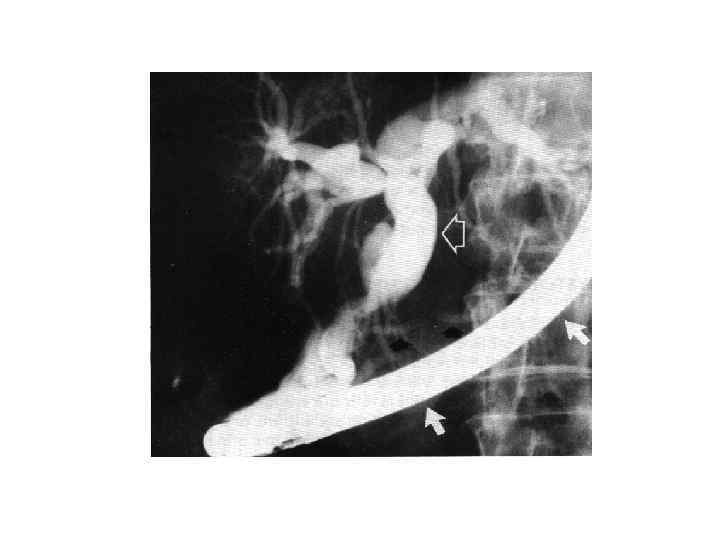

Диагностика • • • Сбор анамнеза Осмотр Обследование передней брюшной стенки Люборатоные данные: общий анализ крови; биохимическое исследование крови, Дуоденальное зоондирование с бактериологическим исследованием всех порций желчи Рентгенологическое исследование УЗИ КТ РХПГ ФЭГДС Лапароскопия радиоизотопное исследование

Диагностика • • • Сбор анамнеза Осмотр Обследование передней брюшной стенки Люборатоные данные: общий анализ крови; биохимическое исследование крови, Дуоденальное зоондирование с бактериологическим исследованием всех порций желчи Рентгенологическое исследование УЗИ КТ РХПГ ФЭГДС Лапароскопия радиоизотопное исследование